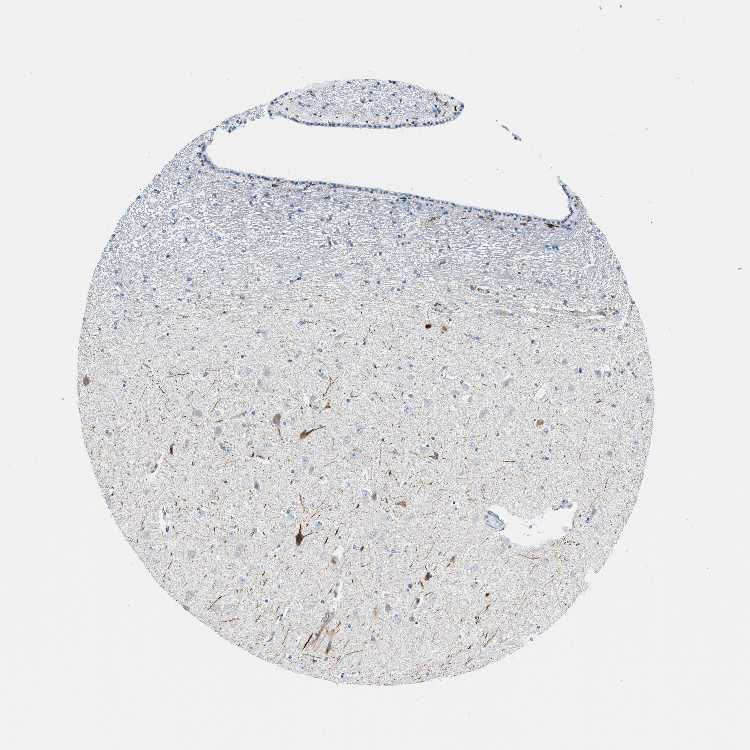

HIPPOCAMPUS - Antibody stainingi

Antibody staining in the annotated cell types in the current human tissue is reported as not detected, low, medium, or high, based on conventional immunohistochemistry profiling in selected tissues. This score is based on the combination of the staining intensity and fraction of stained cells.

Each image is clickable and will lead to virtual microscopy that enables deeper exploration of all samples and also displays staining intensity scores, fraction scores and subcellular localization as well as patient and tissue information for each sample.

Antibody HPA015715

Glial cells Not detected

Neuronal cells Medium